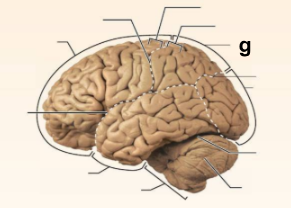

Identify the structure labeled “a” in the image.

Brain Stem

Identify the structure labeled “b” in the image.

Central culcus

Identify the structure labeled “c” in the image.

Cerebellum

Identify the structure labeled “d” in the image.

Frontal lobe

Identify the structure labeled “e” in the image.

Lateral sulcus

Identify the structure labeled “f” in the image.

Occipital lobe

Identify the structure labeled “g” in the image.

Parietal lobe

Identify the structure labeled “h” in the image.

Parieto-occipital sulcus

Identify the structure labeled “i” in the image.

Postcentral gyrus

Identify the structure labeled “j” in the image.

Precentral gyrus

Identify the structure labeled “k” in the image.

Temporal lobe

Identify the structure labeled “l” in the image.

Transverse cerebral fissure